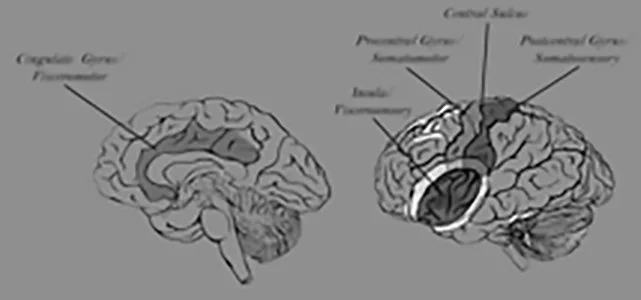

In psychological tasks, such as self-evaluation, the frontal lobe provides regulatory control over emotional responses in limbic regions.

Research in the Brain Electrophysiology Laboratory examines the dynamic changes in frontolimbic activity that discriminates clinically depressed and anxious from normal persons. By understanding these processes, we may be able to guide both biological and cognitive treatments for depression and anxiety.